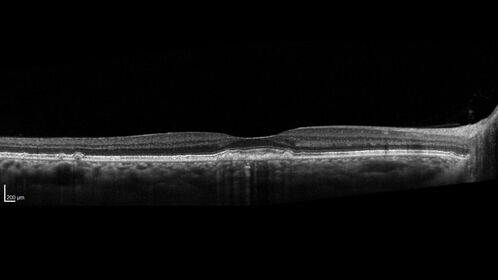

54 year old female with a lot of drusen

VA 20/12 OD, 20/16 OS - no symptoms

54 year old with a lot of drusen